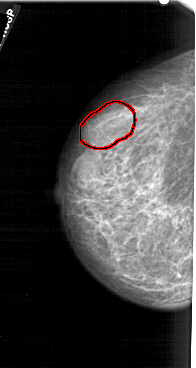

FILE: A_1279_1.LEFT_CC.OVERLAY

TOTAL_ABNORMALITIES 1

ABNORMALITY 1

LESION_TYPE MASS SHAPE LOBULATED MARGINS CIRCUMSCRIBED

ASSESSMENT 4

SUBTLETY 2

PATHOLOGY BENIGN

TOTAL_OUTLINES 1

BOUNDARY

LEFT_CC LINES 5146 PIXELS_PER_LINE 2731 BITS_PER_PIXEL 12 RESOLUTION 43.5 OVERLAY